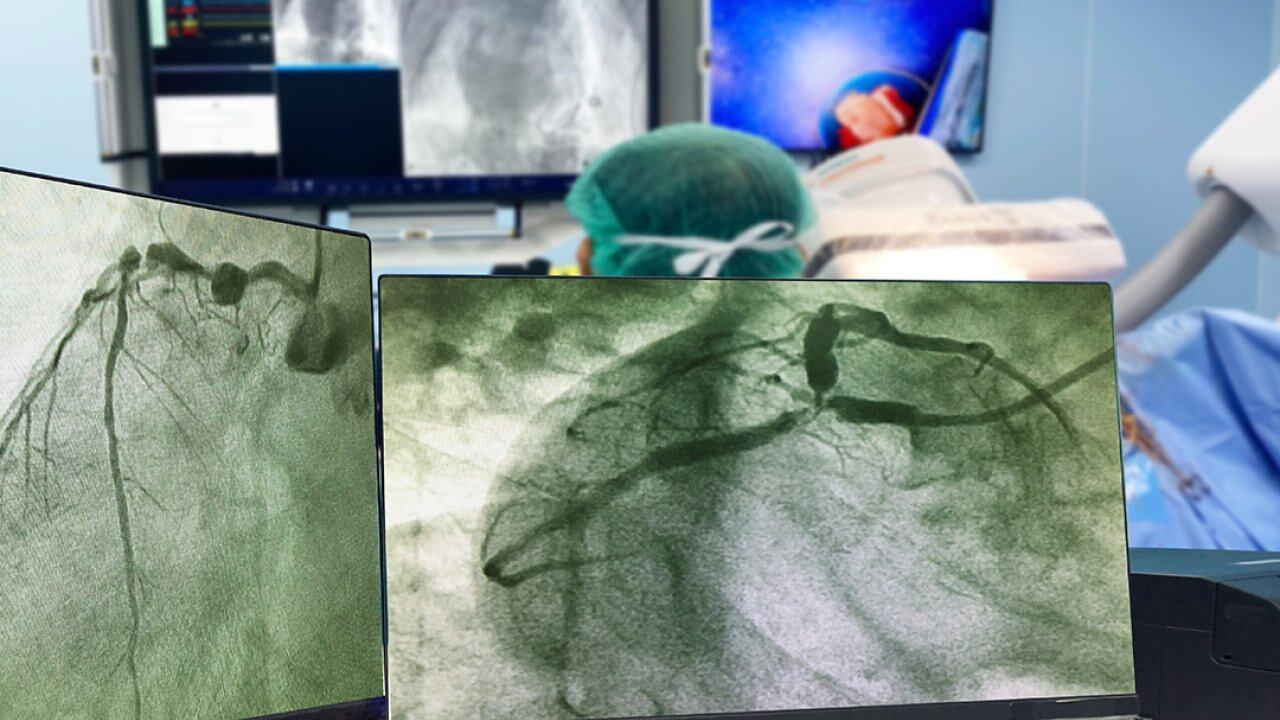

“I’ve got pictures of my heart that clearly show the before and the after,” says Malin. “It’s very alarming how close I was to a tragedy.”

Coronary angiogram

Why you might need it: You're having new or worsening symptoms suggestive of heart disease or received abnormal test results that require further investigation.

How it works: A flexible tube called a catheter is inserted into an artery in your wrist or groin and threaded to the coronary arteries in your heart. Dye is injected to make it easier to get a detailed view of blood vessels on an X-ray image called an angiogram. You'll likely get a light sedative to help you relax. As with Malin, results might lead to the immediate placement of a stent; a short hospital stay may be required.

What it shows: It can detect restricted blood flow to the heart.